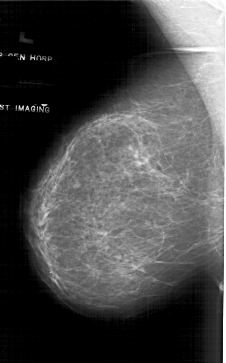

A_1745_1.RIGHT_MLO

RIGHT_MLO LINES 6646 PIXELS_PER_LINE 3991 BITS_PER_PIXEL 12 RESOLUTION 43.5 OVERLAY